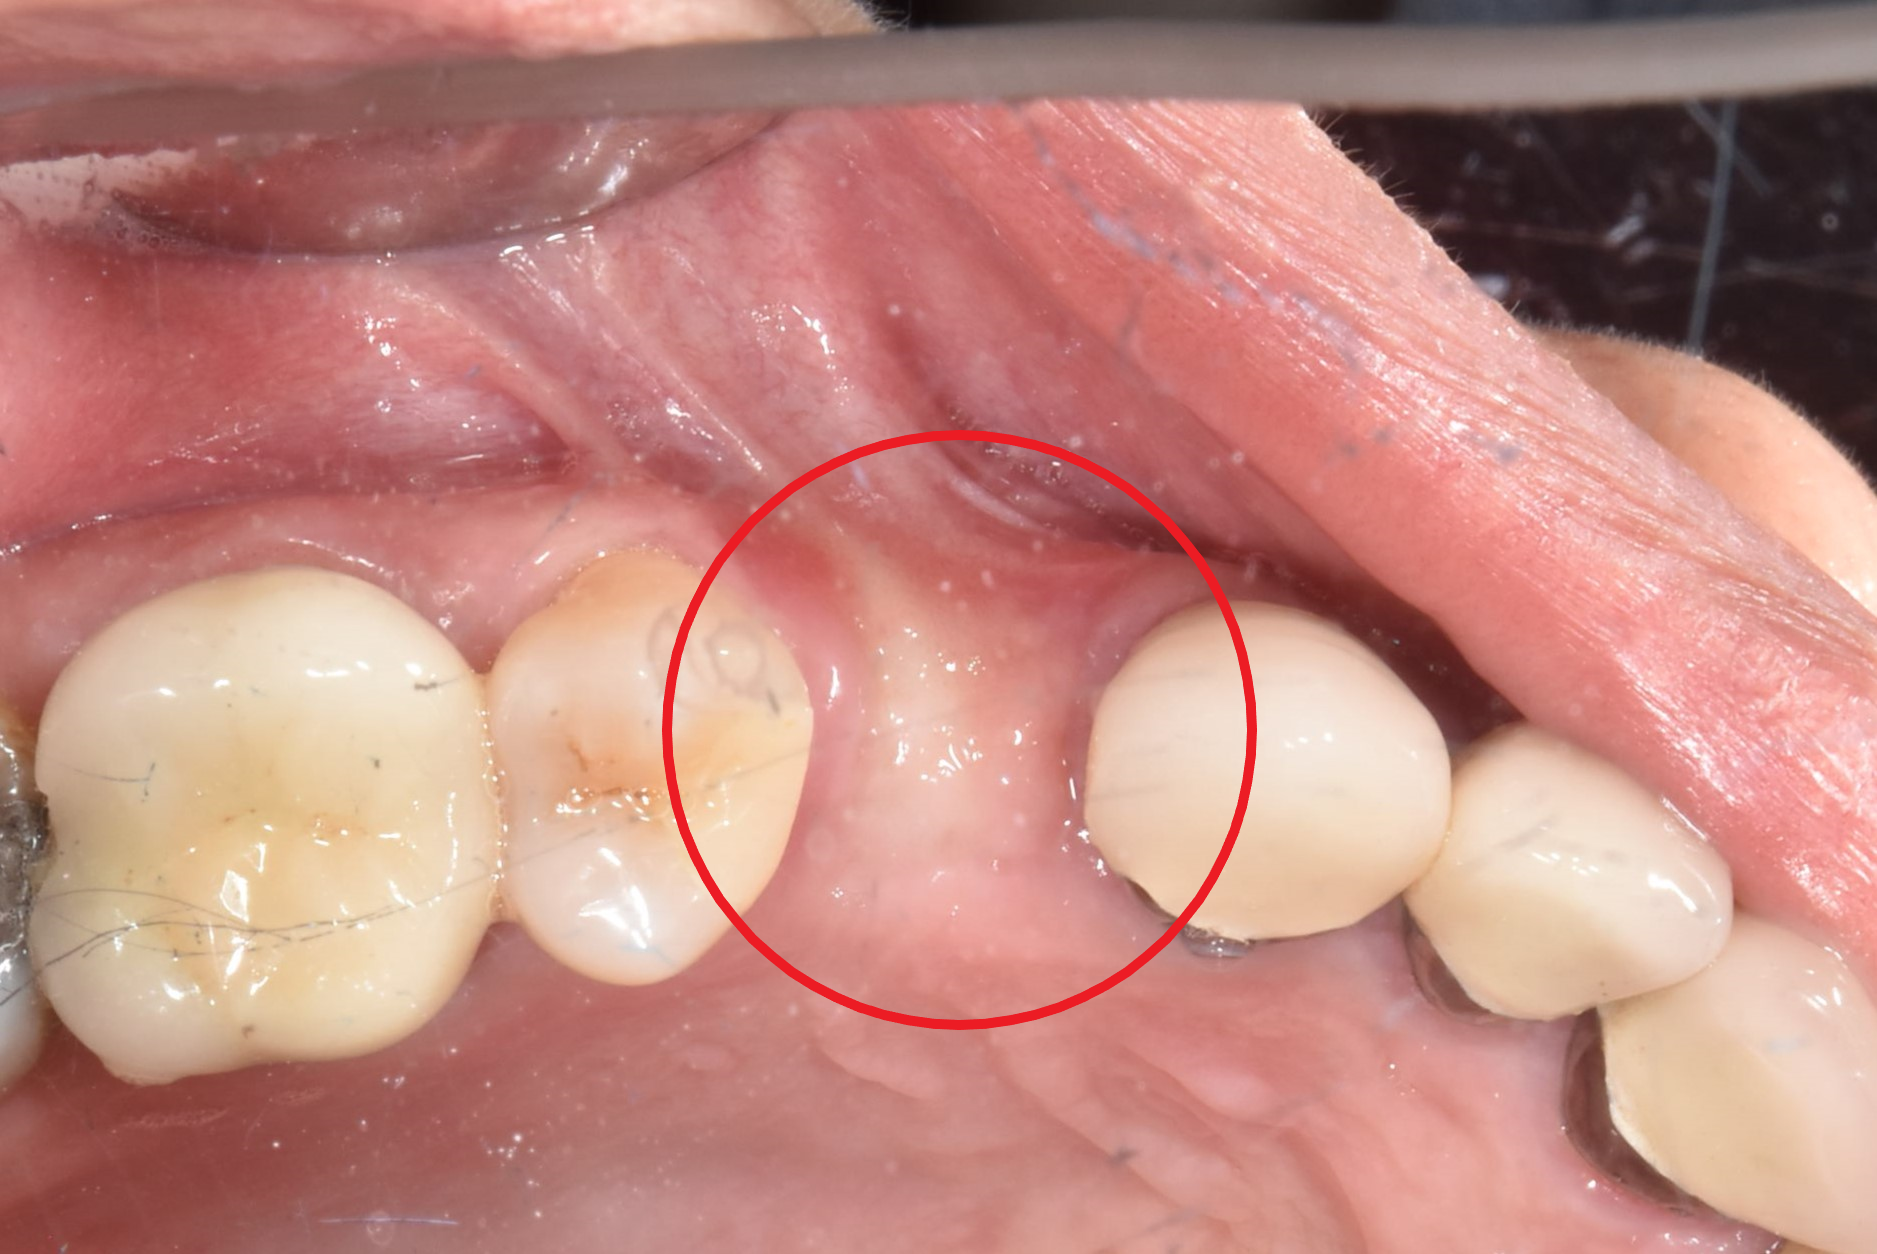

翻瓣補骨的區域

補入所需的骨粉

完成後依骨頭恢復裝況,需定期回診給醫生評估是否進行下一個階段